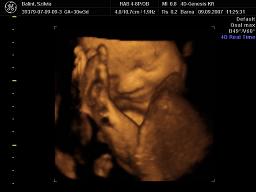

A második képen nyitva van a szeme is

2007.09.28 11:26